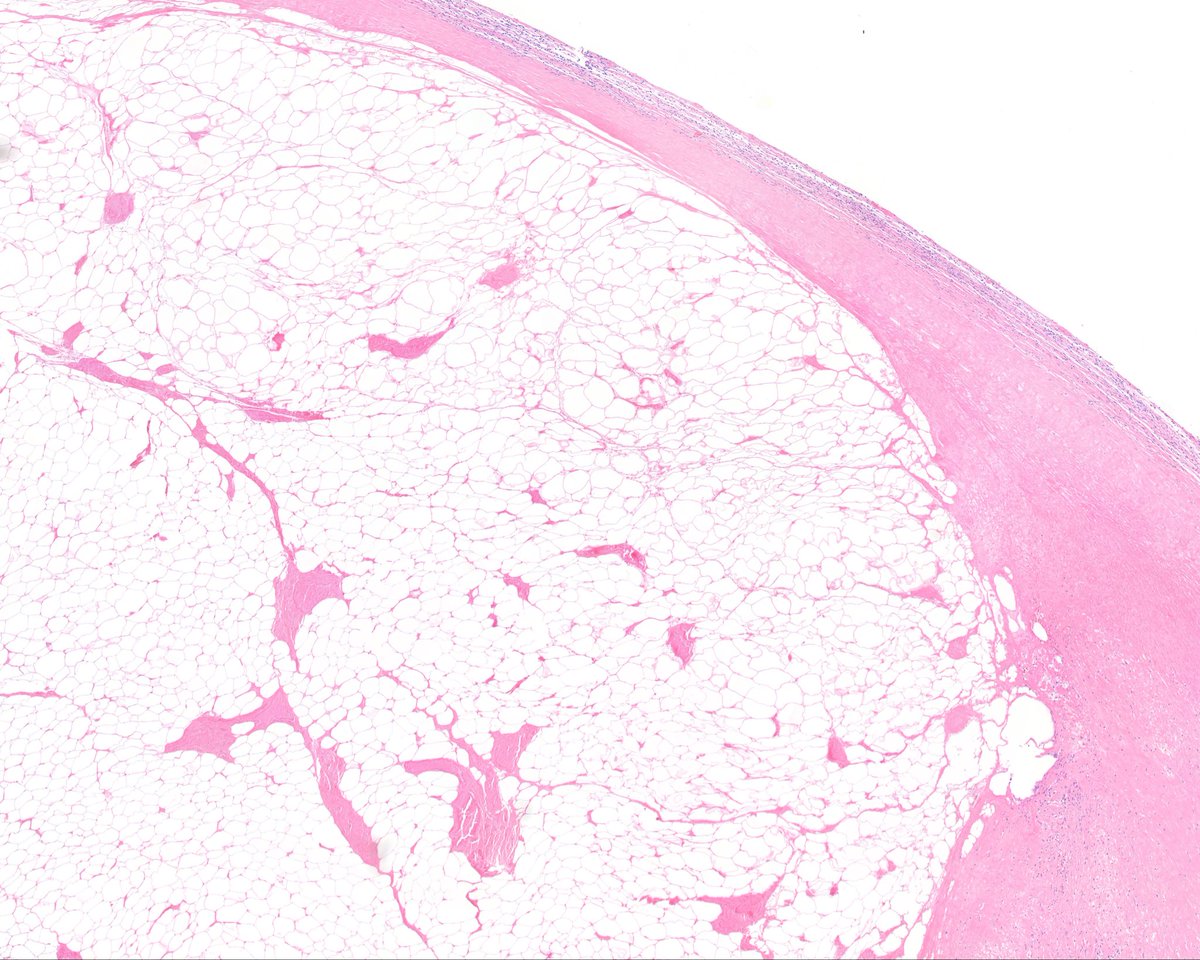

Does This Imaging Make Me Look NFATC2? The Value of... : The American Journal of Surgical Pathology journals.lww.com/ajsp/abstract/…

Does this imaging make me look NFATC2?